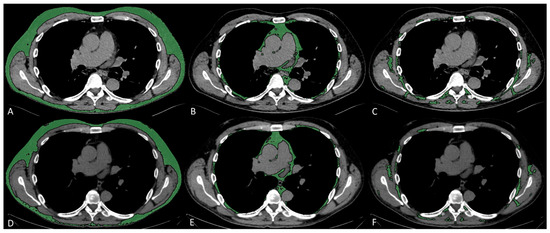

Subcutaneous, visceral, and intermuscular adipose tissue areas (SAT, VAT, and IMAT) were measured on a single slice at the level of the seventh to eighth thoracic vertebrae, by applying a radiodensity range from −190 to −30 HU, through autosegmentation and manual contour correction when necessary. These measurements conducted at T7–T8 showed good reproducibility [17,20], and were previously shown to be representative of total chest fat and moderately associated with abdominal fat [21]. For each fat compartment, mean radiodensity (HU) was also collected. Representative images of fat measurements and respective longitudinal changes are reported in Figure 1.

Figure 1. Fat characteristic measurement. Representative CT images analyzed through semiautomated segmentation of different fat compartments. The measurement of baseline SAT (A), VAT (B), and IMAT (C), and 2–3-month follow-up SAT (D), VAT (E), and IMAT (F), showed a decrease in SAT area from 127 to 107 cm2 and an increase in SAT density from −104 to −90 HU, a decrease in VAT area from 36 to 31 cm2 and an increase in VAT density from −89 to −80 HU, a decrease in IMAT area from 21 to 13 cm2, and an increase in IMAT density from −73 to −61 HU.